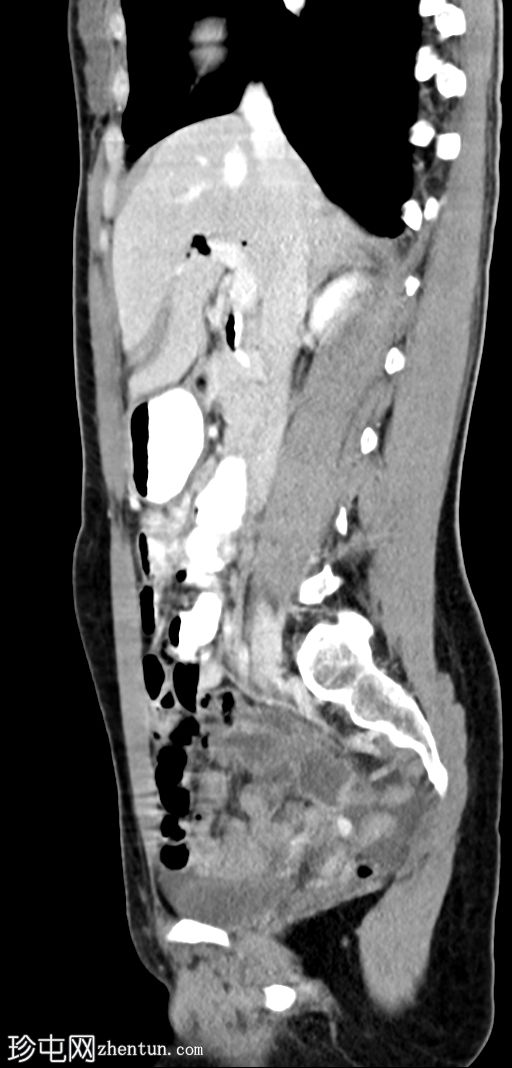

矢状位增强扫描(门静脉期)

肝外胆管、肝内胆管及胆囊内可见气体。后续增强(静脉)检查中加用口服造影剂,结果显示造影剂从十二指肠反流至胆总管,最终进入胆囊。